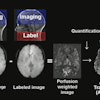

Chronic pain is among the top reasons for visits to physicians worldwide, with up to 43% of chronic noncancer pain patients reporting not receiving treatment. Hybrid PET/MR imaging could help turn this tide over CT and MRI alone, given that it reveals inflammation on a molecular level (PET) combined with highly detailed soft tissue contrast.

The researchers split the participants into two groups, a control arm (n = 14) consisting of standard clinical care without F-18 FDG PET/MRI or an intervention arm (n = 13; 6 LBP patients and 7 THR patients) who underwent the hybrid scans and subsequent clinical management. Potential pain generators were identified by increased F-18 FDG radiotracer uptake on PET combined with anatomical abnormalities on MRI.